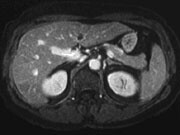

Drug-Eluting Chemoembolization No Better for Hepatocellular CA

No improved survival versus conventional chemoembolization, which has better response rate